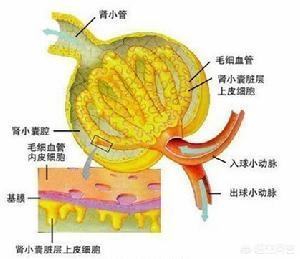

Pourquoi la microalbuminurie est-elle la première atteinte rénale de l'hypertension ? Le glomérule du rein étant en fait un ballon vasculaire, le sang de l'ensemble du corps est filtré par le glomérule pour produire l'urine. Lorsque le glomérule filtre l'urine, il y a une membrane de filtration et, dans des circonstances normales, des substances telles que les protéines ne peuvent pas être filtrées. En cas d'hypertension artérielle, l'augmentation de la pression artérielle endommage les vaisseaux sanguins et, bien sûr, les glomérules, de sorte que la membrane de filtration est endommagée et que les protéines s'échappent. Au début, il s'agit d'albumine de petit poids moléculaire, mais lorsque les dommages sont importants, des protéines de grande taille s'échappent également. Lorsqu'une plus grande quantité de protéines s'échappe, une protéinurie importante se produit et les analyses d'urine de routine révèlent la présence de protéines.

- Les reins sont constitués de glomérules et de tubules. Les glomérules sont comme un tamis qui élimine les déchets dont l'organisme ne veut pas et conserve les protéines dont l'organisme a besoin. L'urine qui passe par le glomérule est appelée urine primaire. Le glomérule est un tamis grossier, et l'urine primaire contient de nombreuses autres substances dont l'organisme a besoin, comme de l'eau et du glucose au maximum, qui doivent être réabsorbées et réutilisées.

- Une fois que les tubules rénaux ont absorbé l'eau et le glucose, l'urine originale est concentrée et devient l'urine finale, qui est excrétée du corps. Le corps humain produit 180 litres d'urine primaire par jour, alors que seulement 1,5 litre d'urine est finalement excrété du corps, ce qui est attribué à la fonction de concentration des tubules rénaux. Si les tubules rénaux sont endommagés, la fonction de concentration est vouée à diminuer, ce qui entraîne une plus grande quantité d'urine.

Lorsque le sang traverse le glomérule, ce dernier équivaut à une membrane de filtration dont les mailles sont très petites, de sorte que les petites molécules telles que l'eau, les électrolytes, le glucose, la créatinine, etc. peuvent être filtrées pour former la proturie, tandis que les cellules sanguines (érythrocytes, leucocytes, plaquettes, etc.), les protéines (albumine, globuline) et d'autres substances relativement grosses ne peuvent pas être filtrées. Bien entendu, cette urine primaire n'est pas l'urine finale que nous excrétons ; les matières premières doivent être réabsorbées et concentrées avant de devenir l'urine que nous excrétons.